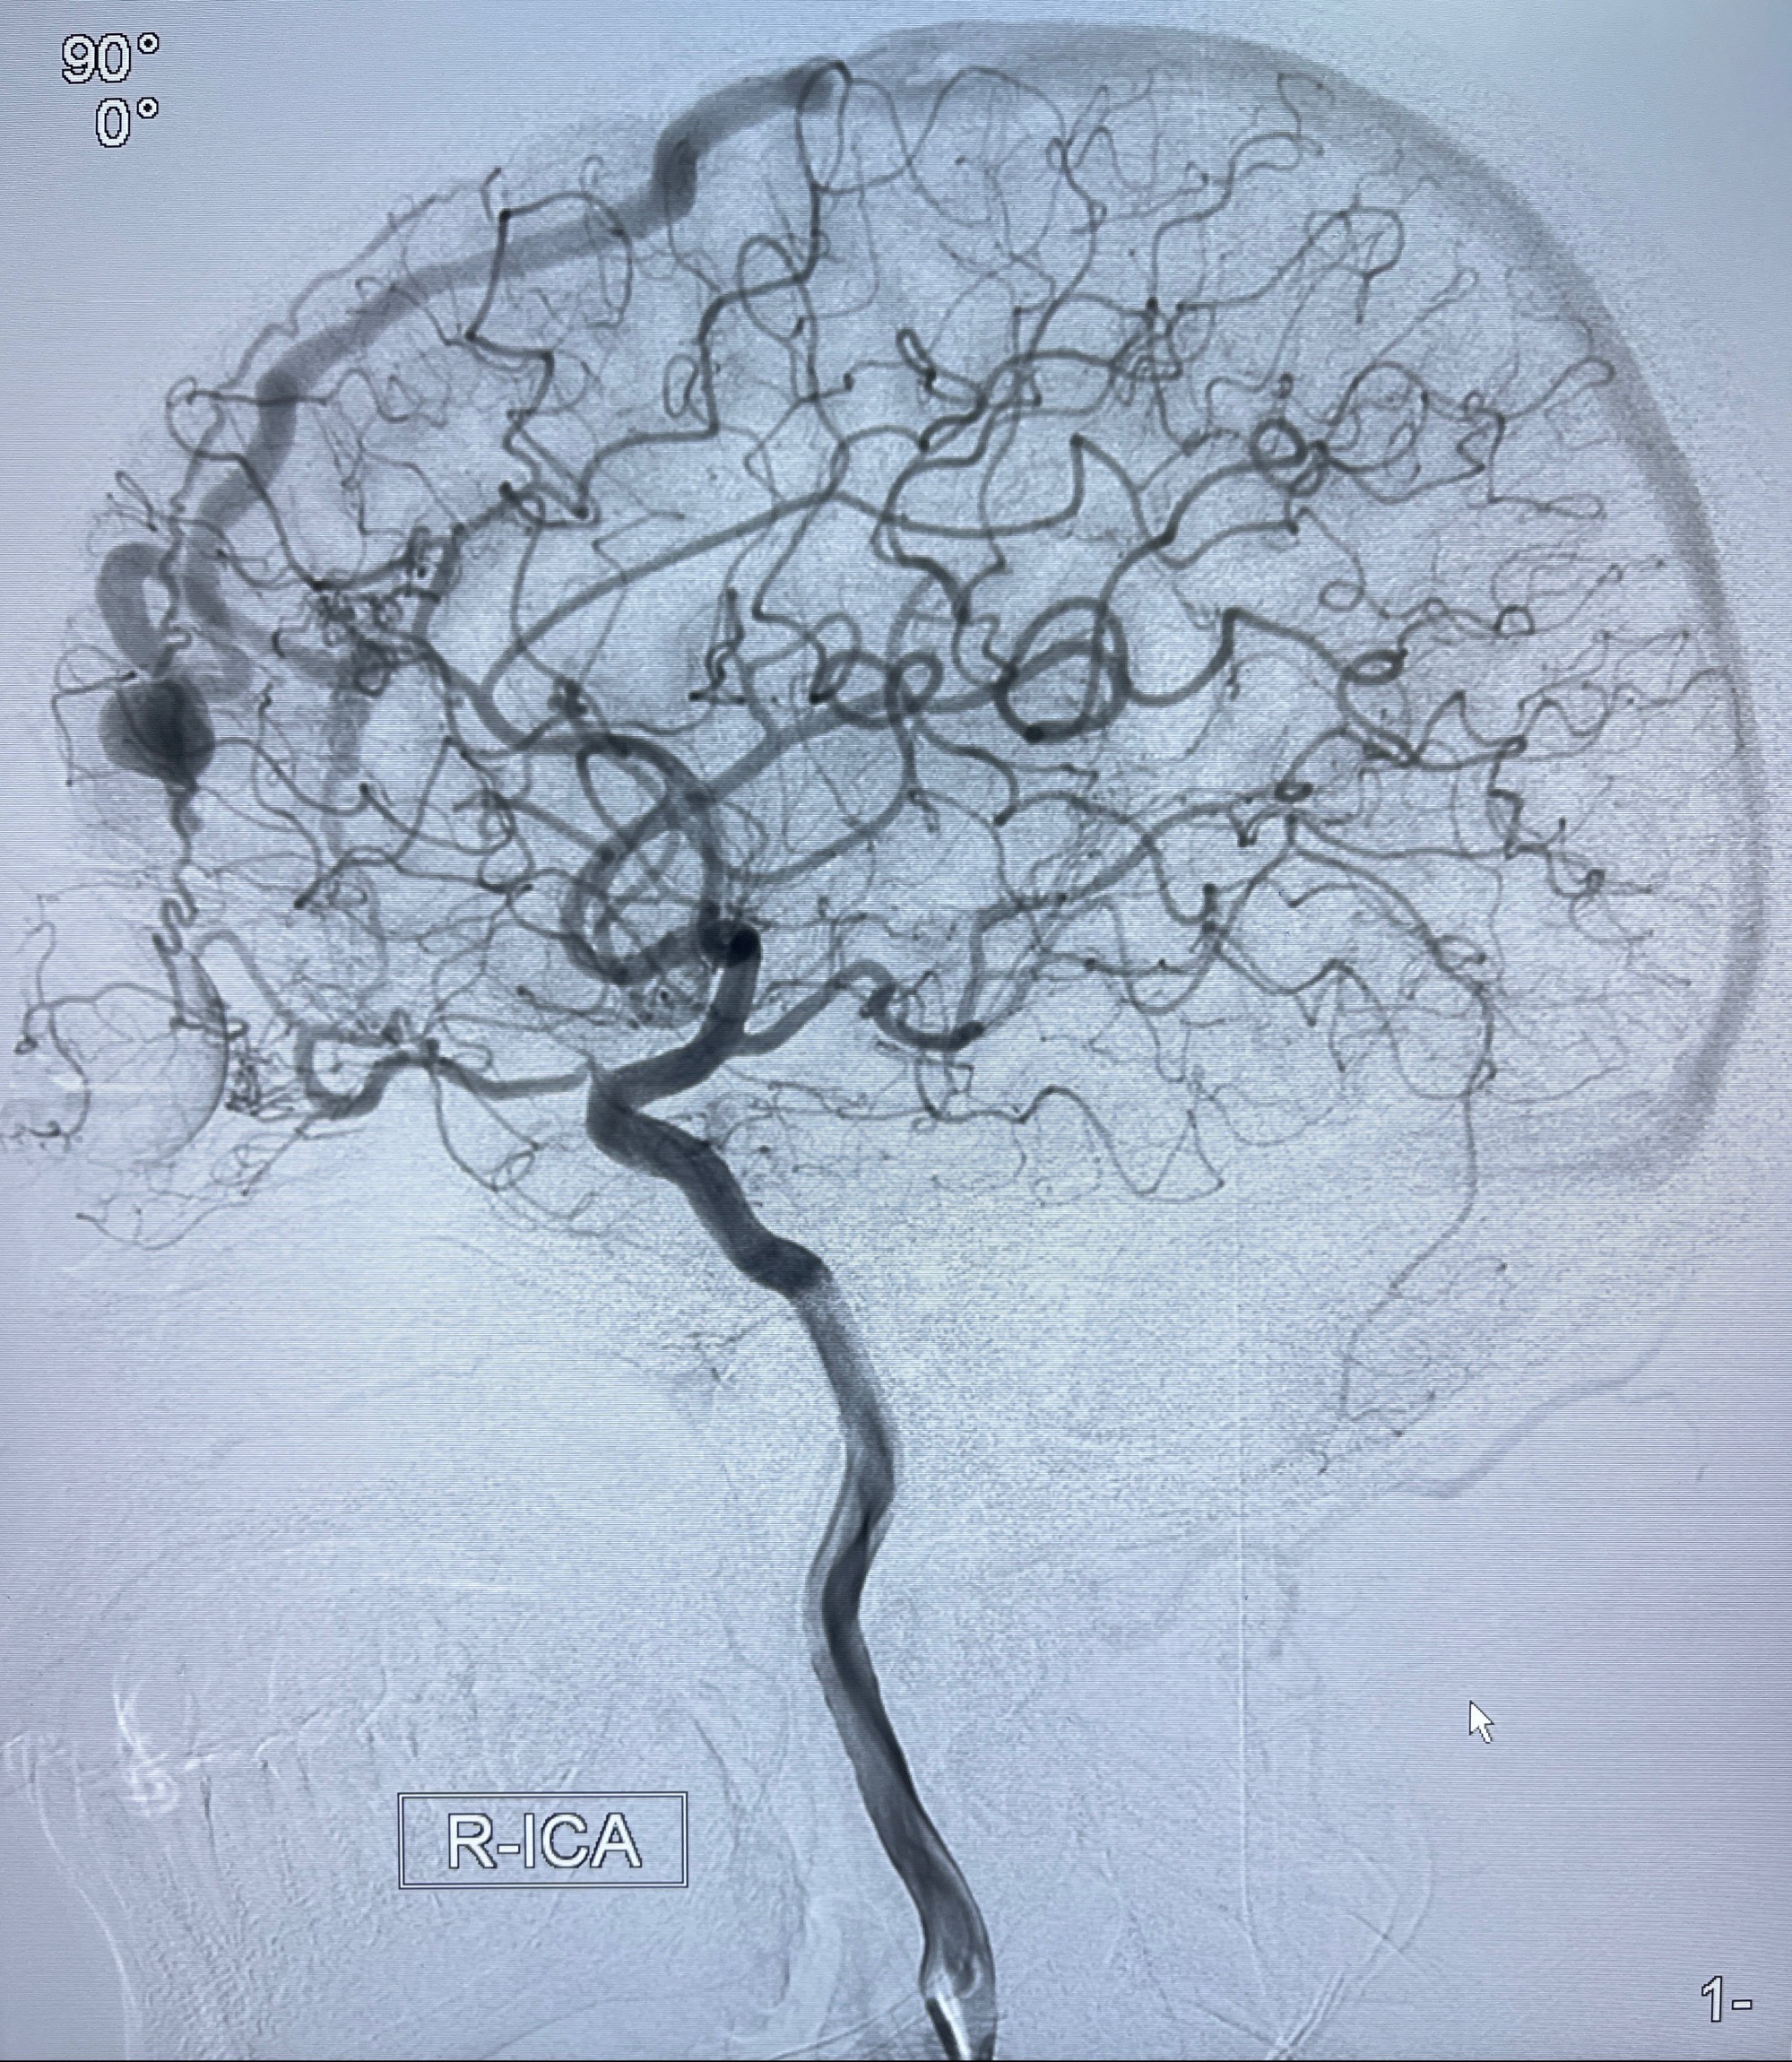

2023年8月21日]景德镇市第一人民医院脑血管造影检查,提示:主动脉弓、双侧颈总动脉、锁骨下动脉造影未见异常,左侧大脑前动脉静脉瘘。

2023-09-13全脑血管造影:前颅底硬脑膜动静脉瘘,供血动脉为双侧胼周动脉、眼动脉脑膜支,静脉向上矢状窦方向引流